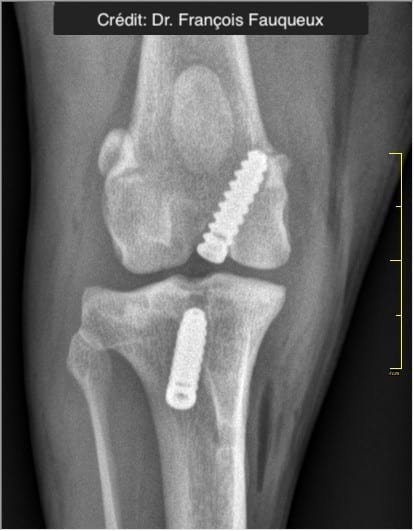

NOVALIG® je syntetický vaz, který lze použít k rekonstrukci vazů a rychlému obnovení jejich fyziologických funkcí.

V případě zkřížených vazů umožňuje intraartikulární rekonstrukci v izometrických bodech připojení, čímž obnovuje biomechaniku kolene a všechny funkce natrženého vazu.

V případě více vazů kolene (kraniální, kaudální, kolaterální) je možné pomocí NOVALIG® anatomicky rekonstruovat každý vaz.

Radiologické snímky